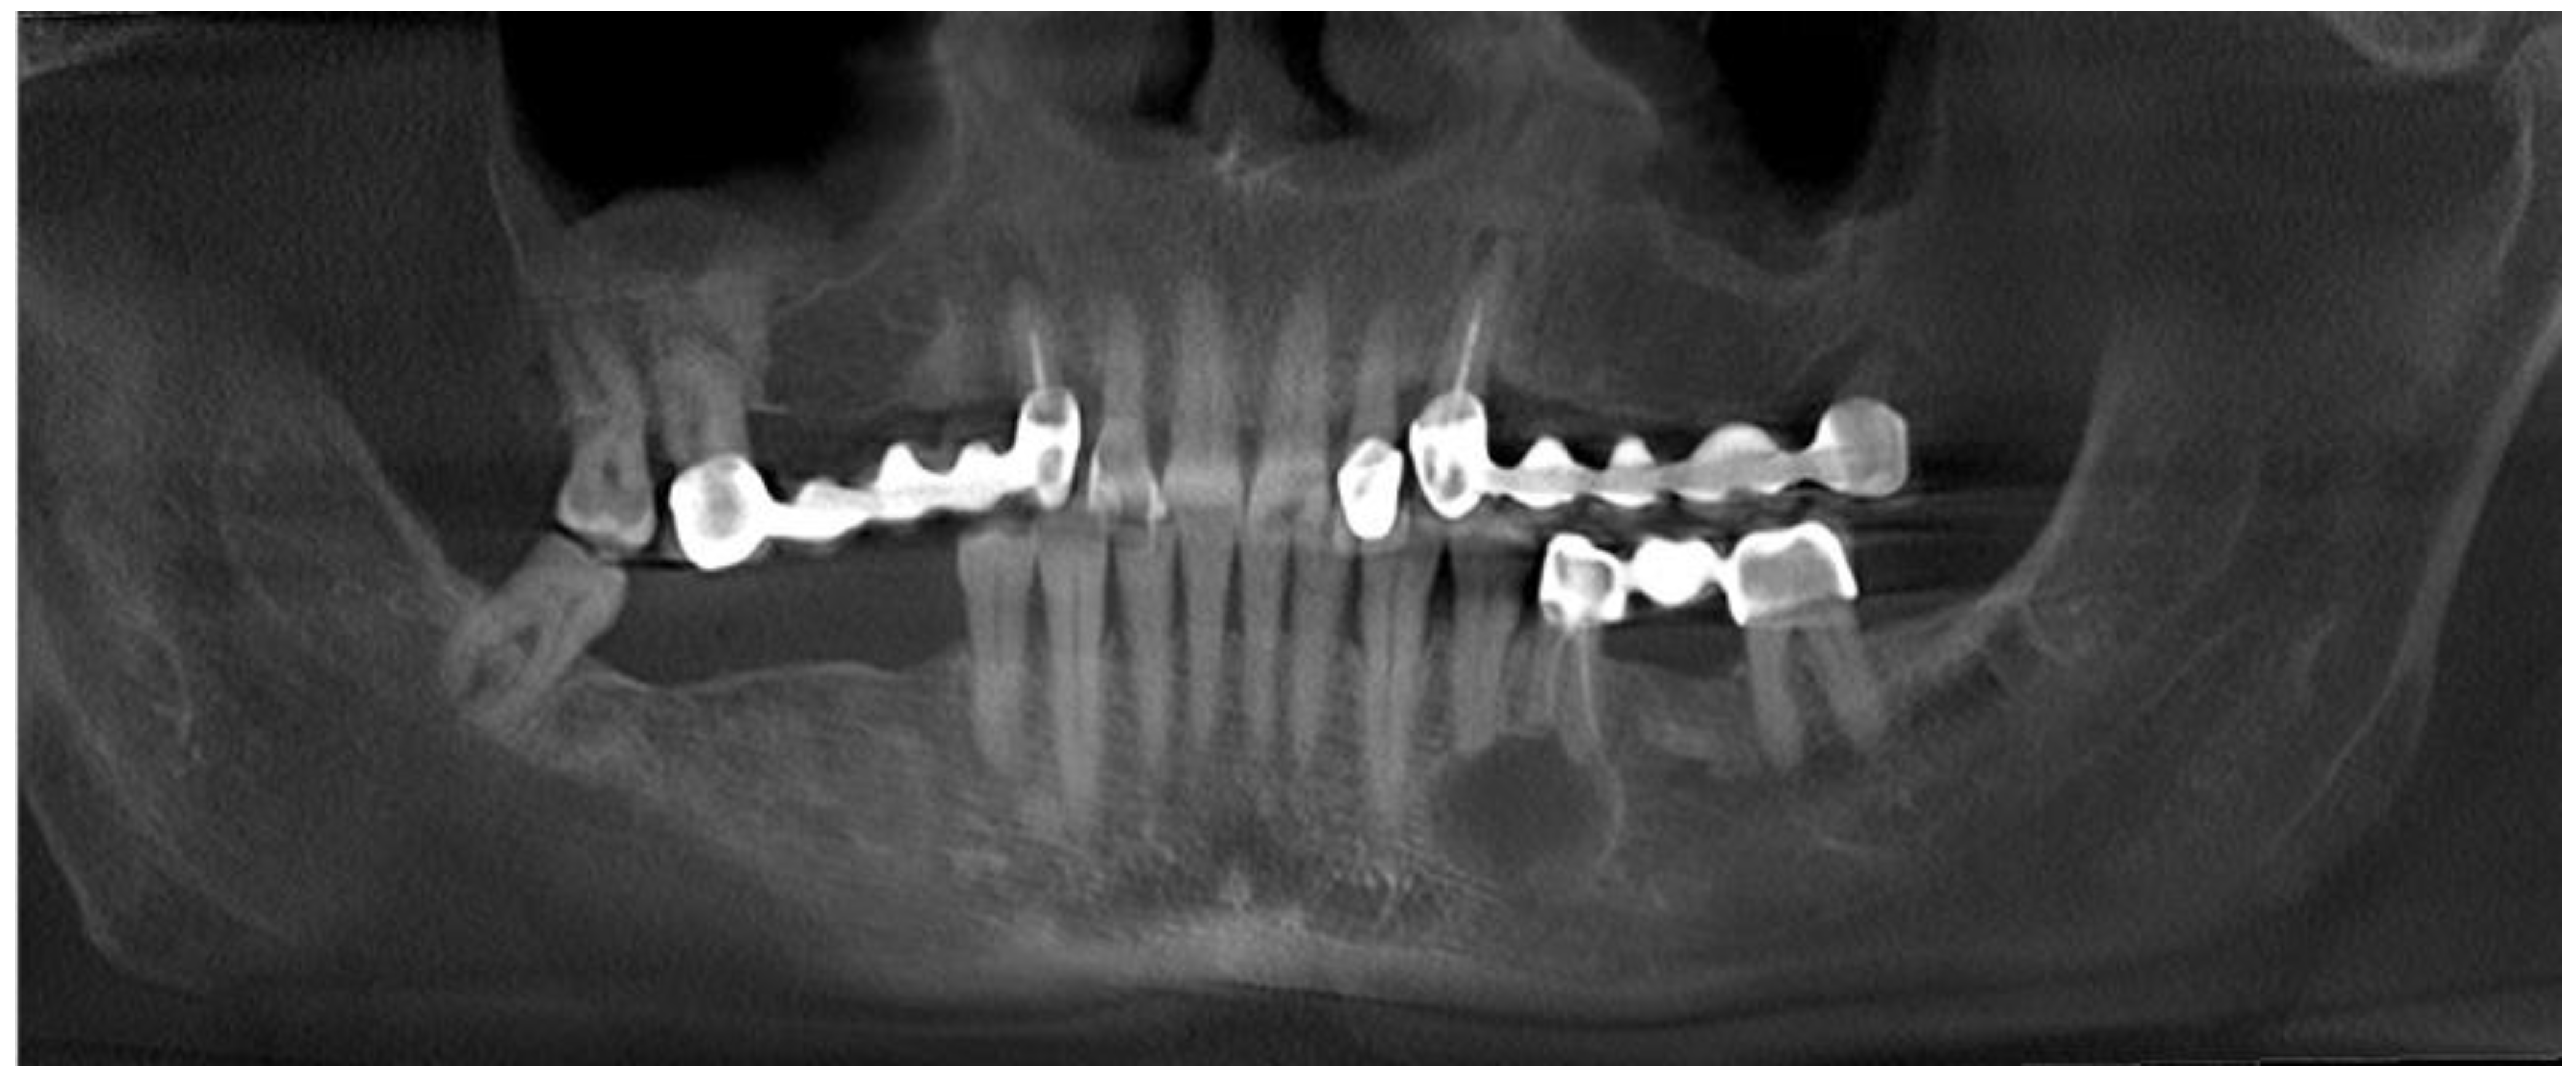

2. Case Description